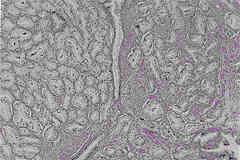

Figure 4: Grade 3 carcinoma (same as shown in Figure 3) showing the usual single layer of cells

around each lumen and showing almost all glands separated by muscle (stroma), seen at higher

magnification.

Illustration courtesy of John E. McNeal, MD, Department of Urology, Stanford University School of Medicine.